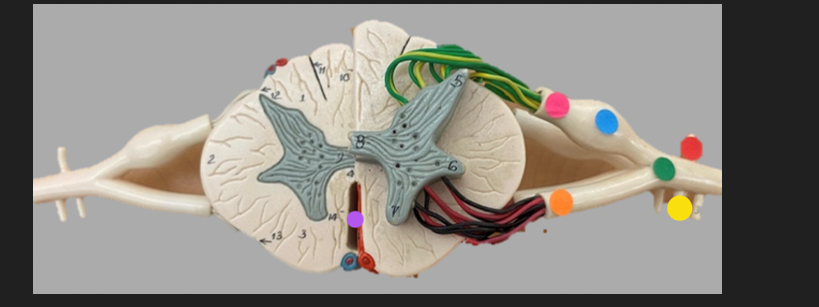

green dot

spinal nerve

orange dot

ventral root

pink dot

dorsal root

blue dot

dorsal root ganglion

red dot

dorsal ramus

yellow dot

ventral ramus

purple dot

anterior median fissure

red dot

posterior (dorsal) horn

purple dot

lateral horn

dark blue dot

anterior (ventral) horn

orange dot

dorsal column

yellow dot

lateral column

dark green

anterior column

line green and pink doit

gray commissure

light blue dot

posterior median sulcus